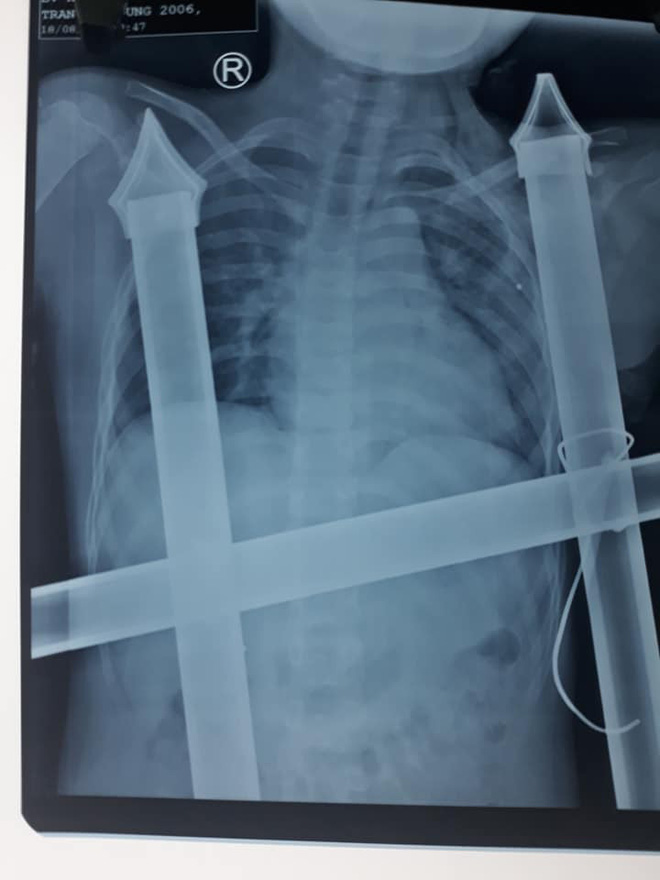

Thời điểm nhập viện, Dũng bị phần chông nhọn của hàng rào dài hơn 10cm đâm xuyên dọc ngực trái. Một phần chông nhọn đã chạm đến nền sọ của bệnh nhân Dũng.

Sau khi chụp chiếu, các bác sỹ đã tiến hành phẫu thuật tháo đầu sắt nhọn ra ngoài và xử lý các tổn thương ở vết thương.

Hình ảnh chụp X-quang.

"May mắn là vật sắc nhọn không làm mạch máu lớn và nội tạng bị tổn thương. Bệnh nhân bị đứt cơ ngực lớn, cọc sắt hàng rào tạo nên đường hầm trong khoang ngực kéo dài trên 10cm.

Chúng tôi đã rút được dị vật ra khỏi cơ thể cậu bé an toàn. Đồng thời, lau rửa, sát trùng vết thương, dẫn lưu đường hầm, khâu cơ ngực lớn và da liền lại", BSCKI. Hồ Thái Phúc (khoa Phẫu thuật Tim mạch lồng ngực) cho biết.